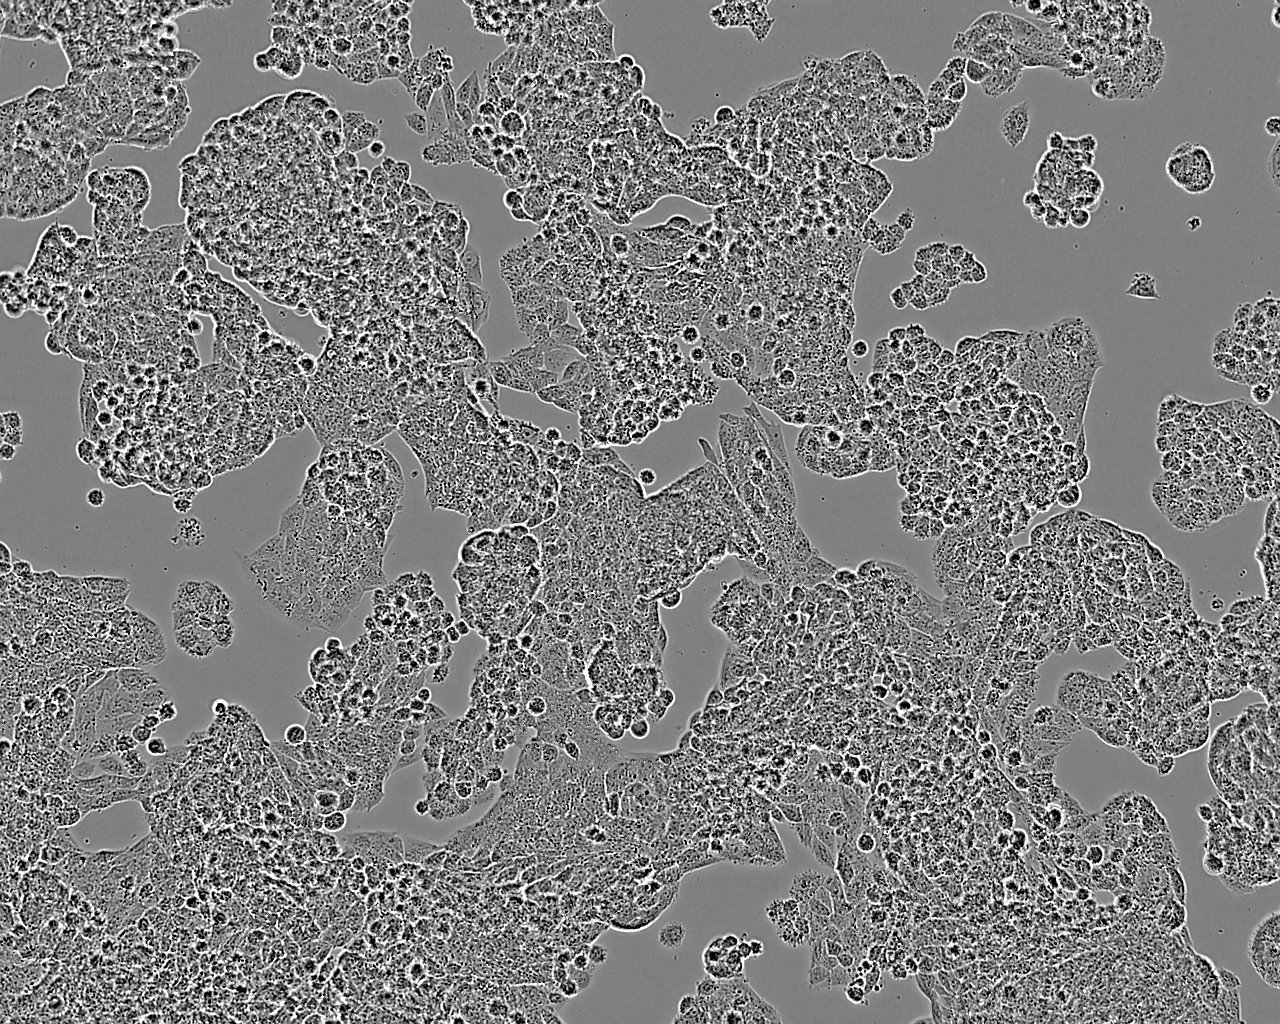

A2780人卵巢癌細胞(STR鑒定正確)

• 形態(tài)特征: 上皮細胞樣

• 生長特性: 貼壁

培養(yǎng)時會有細胞碎片

從一位未接受治療的患者的癌組織中分離建系。細胞會單層生長,在搖床培養(yǎng)時可懸浮生長。可用作抗藥藥物敏感性研究模型。